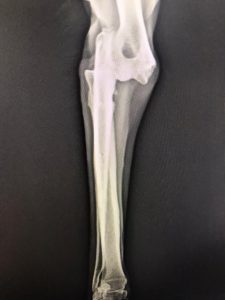

Yine Konya Akşehir

Tedavi